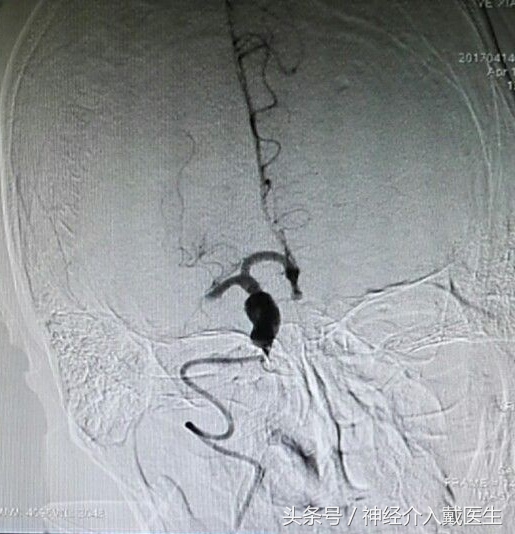

支架机械取栓治疗是目前治疗急性脑梗死的最为先进的技术手段,和溶栓治疗相比具有安全性高、作用显著和时间窗长等优点,目前已在国内外大型医疗中心普及。支架机械取栓是将一条直径0.3毫米左右的导丝从患者股动脉穿入体内,在透视监示下通过脑内大血管中的血栓进行定位,再用微导管将镍钛合金的取栓支架输送到血栓部位,释放支架后,镍钛合金支架自动膨胀展开,形成圆柱形网状结构,与血管壁贴合、嵌入血栓。术者将取栓装置抽离,栓子同时被拽出体外。